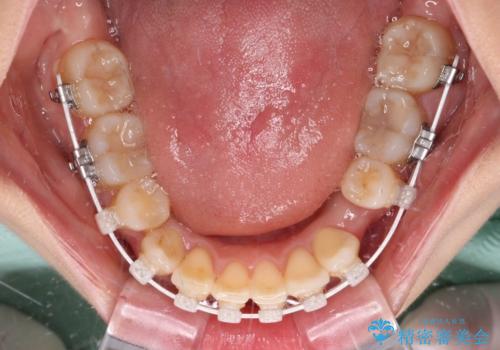

デコボコで磨きにくい歯列 ワイヤー装置での抜歯矯正で歯磨きをしやすく

- デコボコの歯列で歯磨きがしにくいことを気にして来院された患者様です。

右側の上下は歯が重なり合って、内側に移動してしまうほどであり、それに伴って正中の位置が右側にずれている状態でした。

上下左右の第一小臼歯4本を抜歯して行うことになりますが、それだけでは咬み合わせの改善や正中位置の改善が困難であると判断されたため、アンカースクリューを用いた補助装置を併用することで、スムーズかつより良い仕上がりを目指すこととしました。

途中むし歯が見つかり、矯正治療を行いながら迅速に対応し、何とか神経組織を保存して治療を終えることができました。